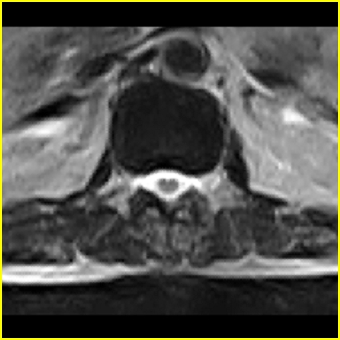

男,78岁,右下肢跛行两月.

右侧黄韧带肥厚或钙化,压迫马尾神经所致。必要时行ct扫描。

腰间盘膨出、黄韧带肥厚、可疑先天性腰椎管狭窄。

退行性病变:增生、椎间盘变性、膨出[l4-5、l5-s1 椎间盘膨出]

我认为这一层面椎间盘应该合并左外侧型突出。